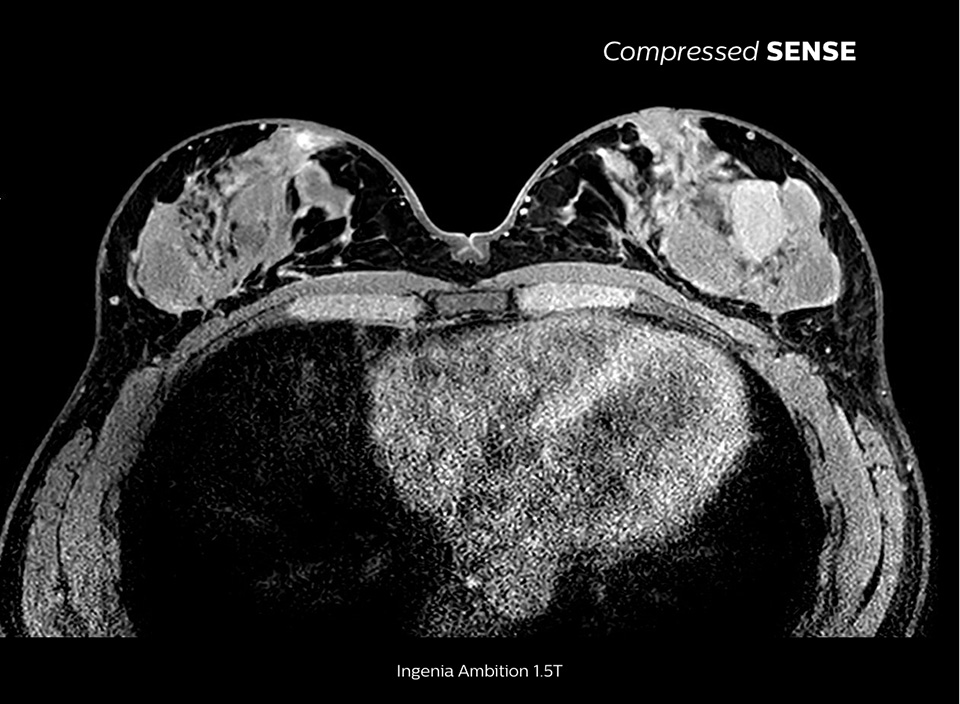

The MRI staff at Kurashiki Central Hospital incorporated Compressed SENSE into most of the brain, spine, abdominal, and cardiac examination protocols on their Ingenia 1.5T, resulting in fast and high-quality MRI scans, which is welcomed by patients and staff.